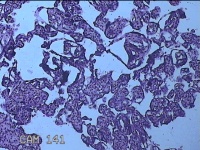

胎盘组织

性别

女

年龄

30岁

临床诊断

妊娠合并中度贫血

一般病史

停经39+2周,B超检查发现羊水偏少6小时。

标本名称

大体所见

灰白暗红色胎盘组织16.5x14.5x3.5㎝一个,表面光滑,血管突出,颜色发暗,绒毛面结节状,有轻度糜烂,暗红色,有少许凝血块,切面见绒毛内有暗红色血液渗出,边缘蜕膜可见多个小血肿,脐带39x1.8x0.3㎝,螺旋状扭曲,切断脐带,见脐血管内有凝血块。